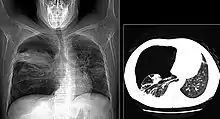

X-ray and CT of ground glass opacities and pneumothorax in pneumocystis pneumonia

Diagnosis of Pneumocystis pneumonia is by identifying the organism from a sample of sputum, fluid from affected lungs or a biopsy.[4][3] A chest X-ray of affected lungs show widespread shadowing in both lungs, with a "bat-wing" pattern and ground glass appearance.[2][7] Giemsa or silver stains can be used to identify the organism, as well as direct immunofluorescence of infected cells.[3]